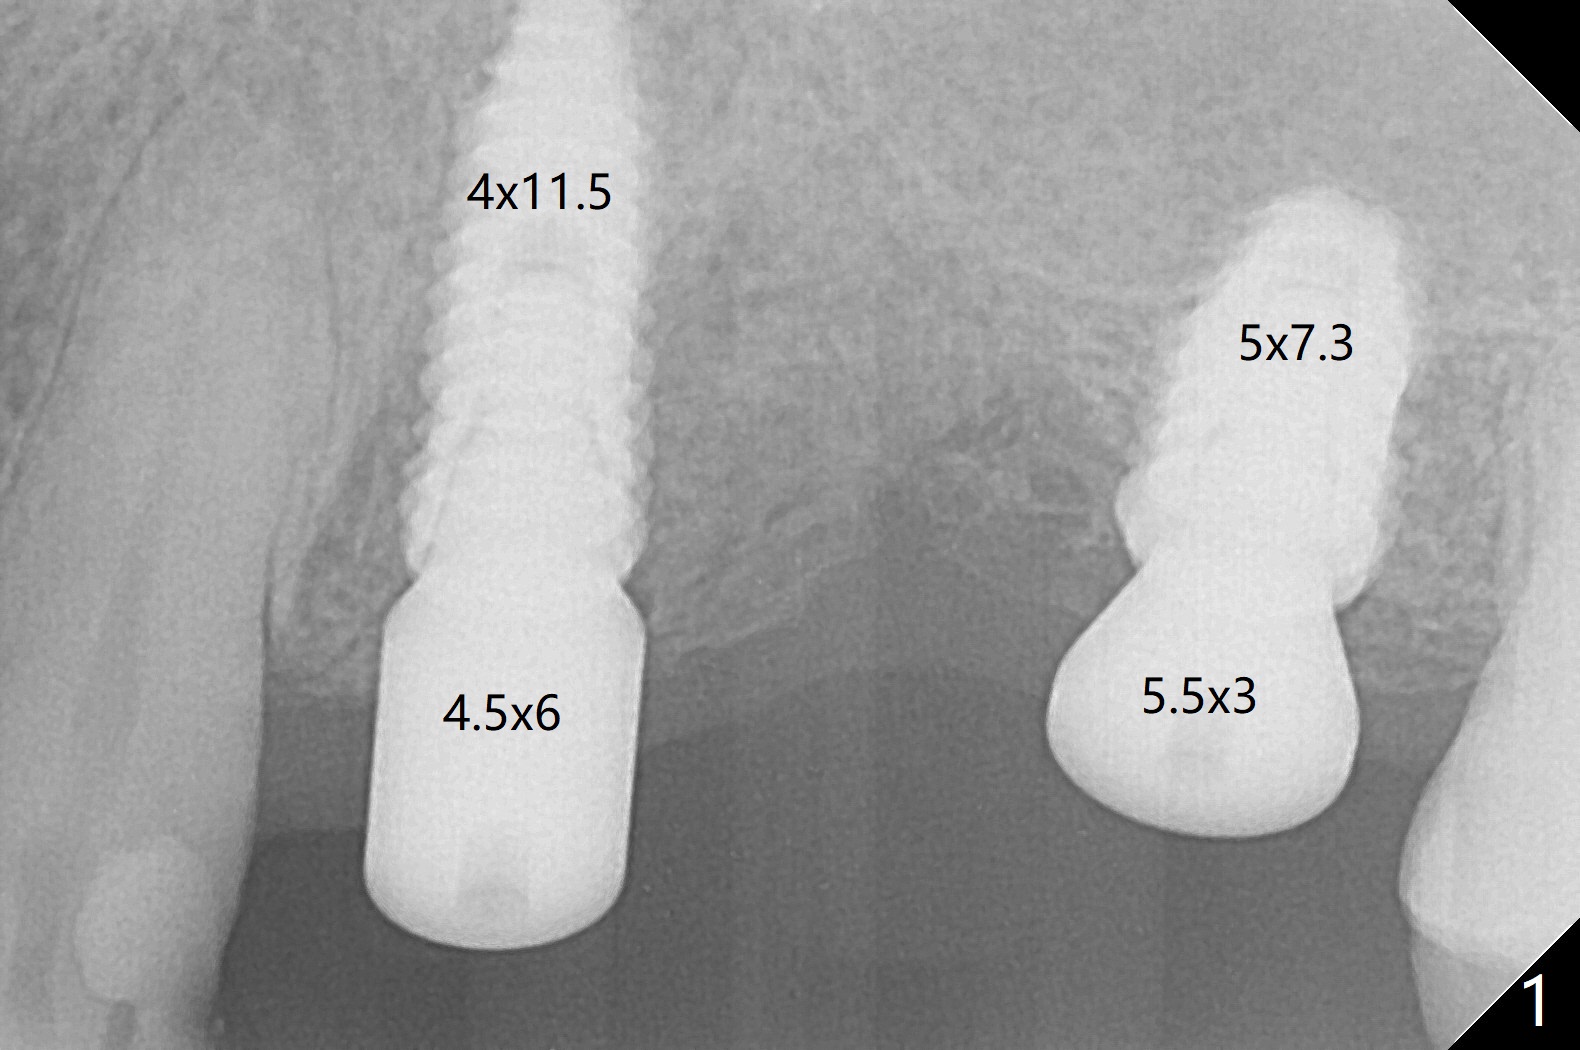

With 34 mg of Lidocaine and 17 mcg of Epinephrine, implants are placed at #12 and 14 without discomfort (45 and 15 Ncm, Fig.1). Since the bone density at #12 is higher than that at #14, implant is placed at #12 first. With fixture anchor pin placed at #12, osteotomy and implant placement at #14 is much easier than those at #12 because of one free hand. Probably due to limited mouth opening and TMJ dislocation, these two implants are not placed in parallel.